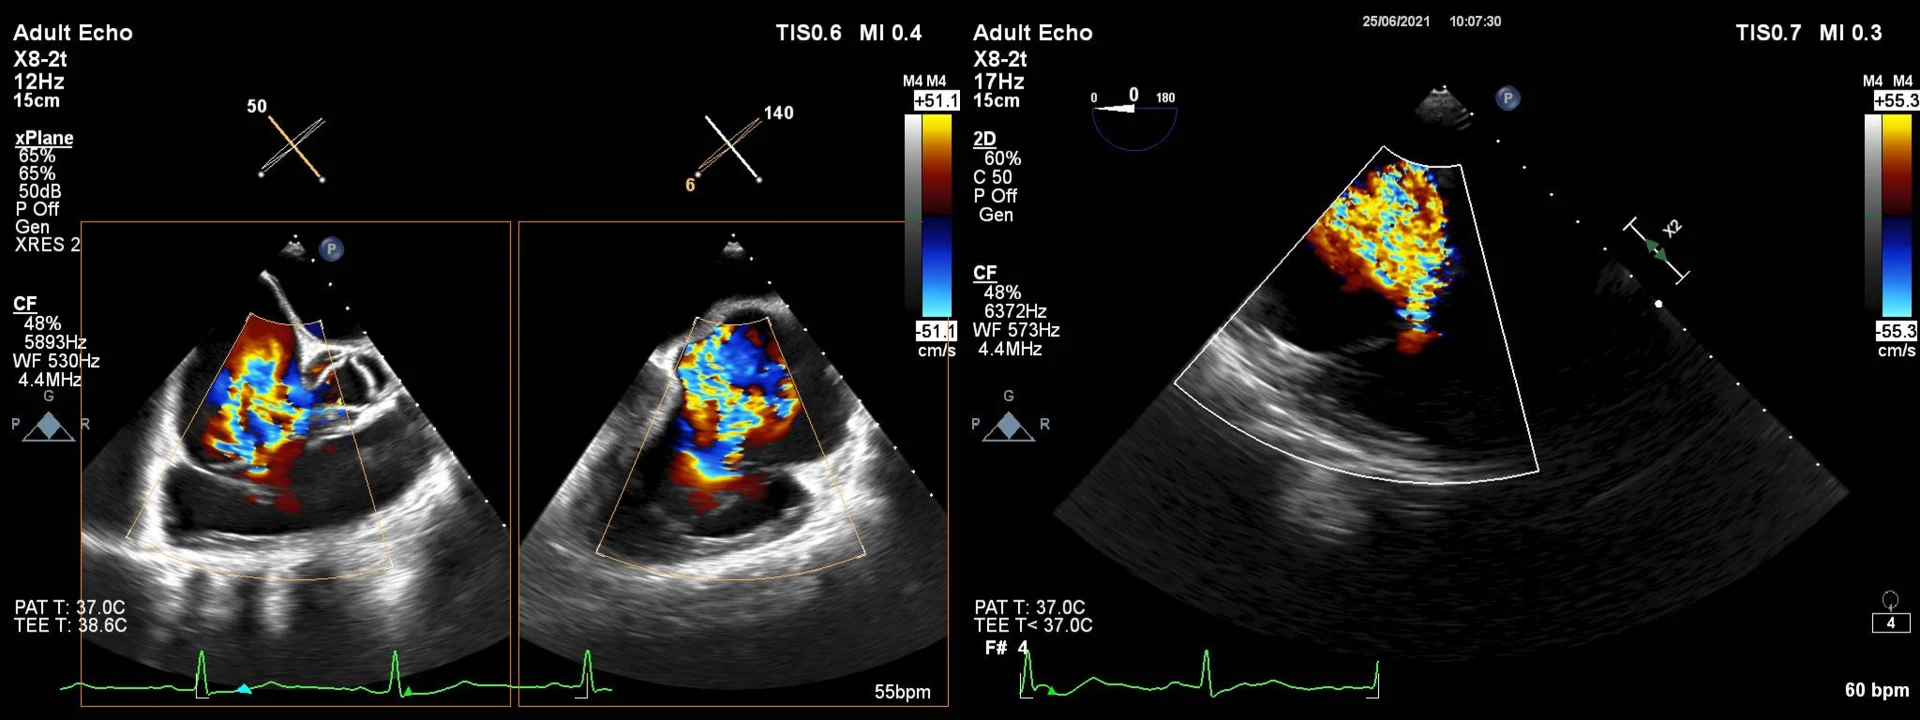

Τι είναι η ανεπάρκεια της τριγλώχινας βαλβίδας;

Η ανεπάρκεια της τριγλώχινας βαλβίδας είναι μια καρδιακή πάθηση κατά την οποία η τριγλώχινα βαλβίδα, που βρίσκεται ανάμεσα στον δεξιό κόλπο και τη δεξιά κοιλία της καρδιάς, δεν κλείνει σωστά. Αυτό έχει ως αποτέλεσμα μία ποσότητα αίματος να παλινδρομεί από τη δεξιά κοιλία στον δεξιό κόλπο όταν η κοιλία συστέλλεται, αντί να προωθείται προς τους πνεύμονες για οξυγόνωση.